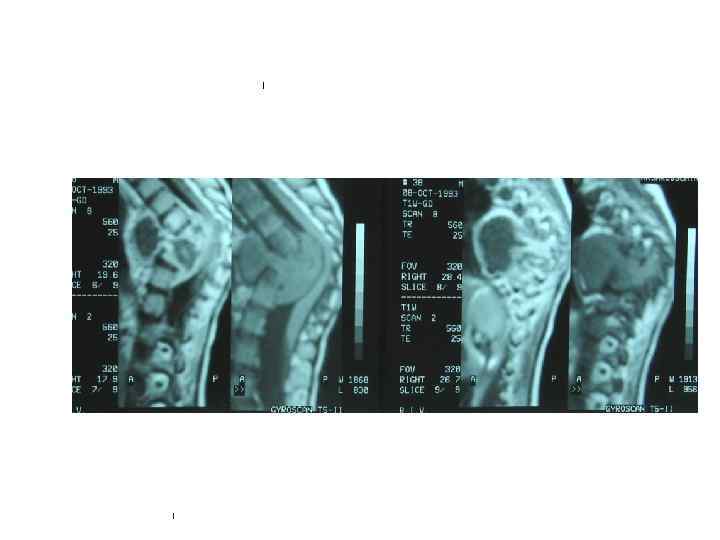

АБДОМИНАЛЬНЫЕ ФОРМЫ ТУБЕРКУЛЁЗА туберкулёзный мезаденит, туберкулёзный перитонит, туберкулёз кишечника. • В кишечнике туберкулёзные бугорки и инфильтраты формируются в подслизистой оболочке подвздошной и слепой кишок с последующим распадом и рубцеванием. • Достоверные R-признаки при мезадените– обызвествлённые лимфатические узлы на снимках брюшной полости или при рентгеноскопии. • Менее достоверные симптомы туберкулезного мезаденита - нарушения моторики кишечника, динамическая непроходимость, опущение желудка и поперечно-ободочной кишки. • Существенное значение имеют: данные МРТ и КТ (визуализируются пакеты внутрибрюшных лимфатических узлов, в т. ч обызвествленные)

Туберкулезный мезаденит • обызвествлённые лимфатические узлы в брыжейке ободочной кишки • туберкулёз лимфатических узлов в фазе инфильтрации с очаговым обсеменением брюшины (эндофотограмма)